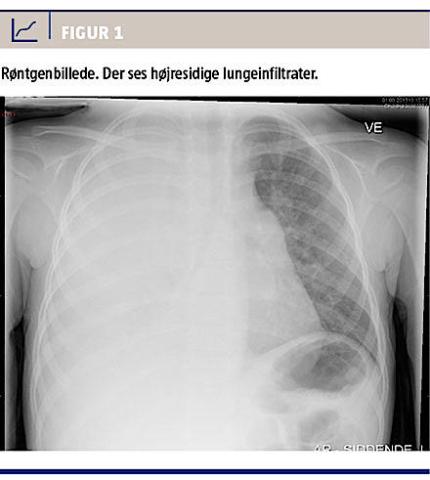

Dagen efter henvendte familien sig igen på afdelingen, da pigen hverken havde spist eller drukket. CRP-koncentrationen var steget til 116 mg/l og koncentrationen af de neutrofile granulocytter til 13,3 × 109/l. Ved en røntgenundersøgelse (Figur 1) sås højresidige lungeinfiltrater. Herpå blev der påbegyndt i.v. benzylpenicillin (1 mio. enh. × 3)-behandling. Pigens tilstand bedredes en anelse i løbet af de næste to dage, med temperaturfald til 38-38,5 °C. På den trejde indlæggelsesdag blev hun atter højfebril, CRP-koncentrationen var 102 mg/l, og koncentrationen af neutrofile granulocytter var 33,9 × 109/l. Efter konference med mikrobiologer ændredes behandlingen til i.v. cefuroxim (400 mg × 3) og gentamycin (60 mg × 1).